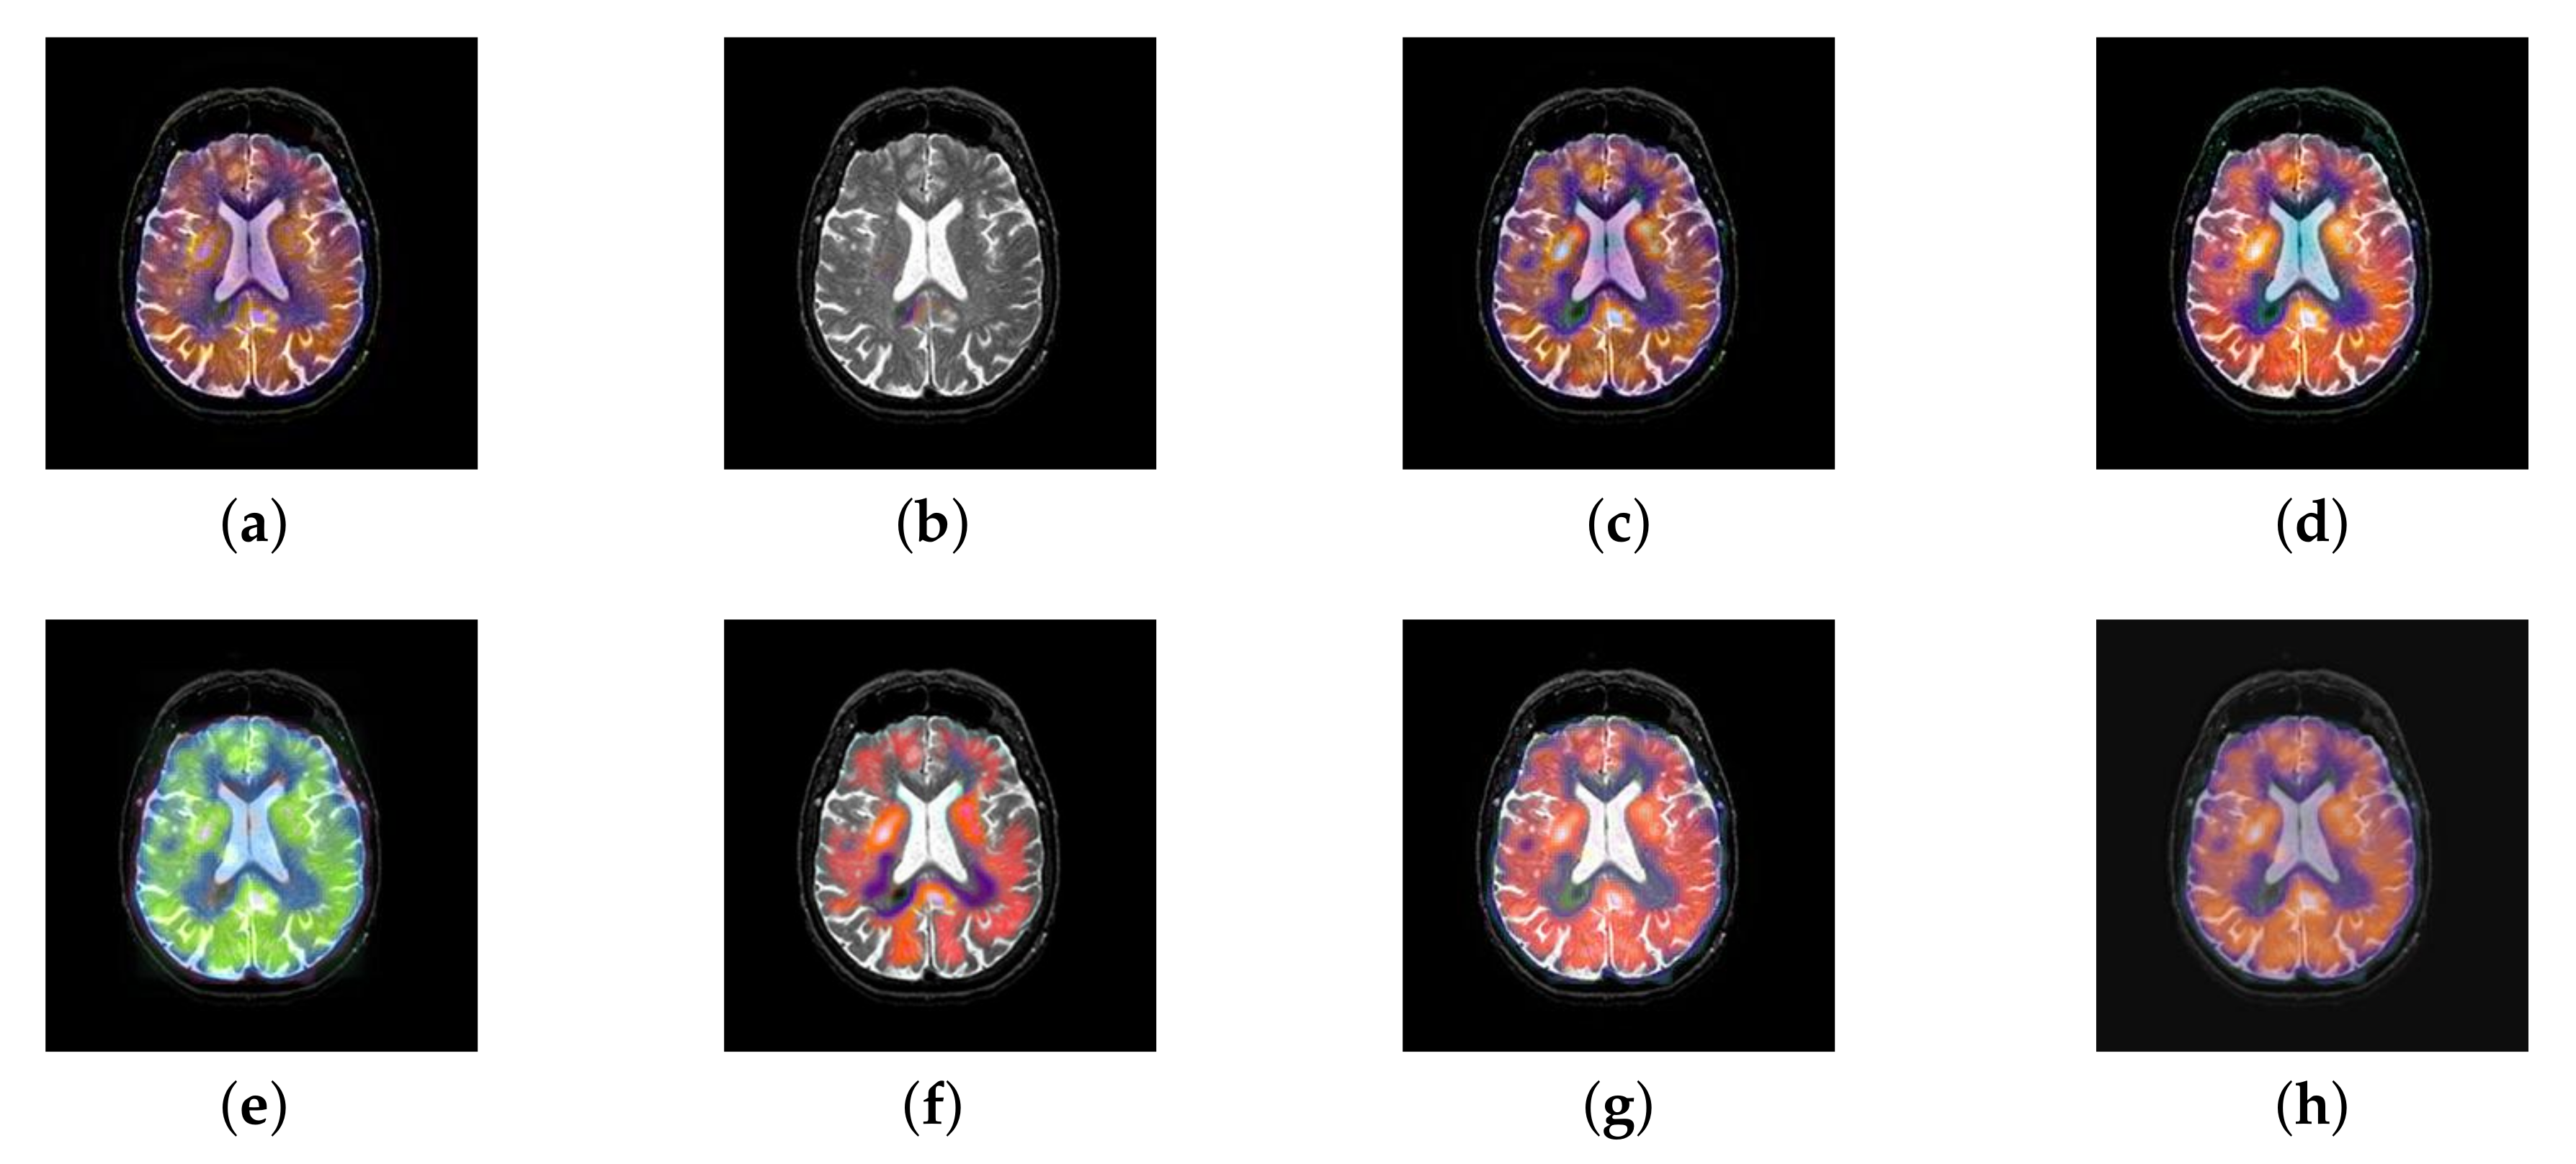

In this section, there are four image sets to fuse, each containing a MRI image and its corresponding CBF image in Figure 41. In Figure 42, Figure 43, Figure 44 and Figure 45, it can be seen that the structural information of fusion images obtained by our algorithm is complete. The color is not distorted, and the spectral features are natural. The fusion image based on DTCWT and NSCT algorithm have high color fidelity but less structural information. Other algorithms, such as IGM, LPSR, and FusionCNN, only focus on the structural information of the MRI image and ignore the color information of the fused image. Although the image structure information obtained by DDcGAN fusion algorithm is relatively complete, the edge of color information is not clear, which has a great influence on image contrast.

Figure 42.

Fused medical images obtained by different algorithms (Figure 41a,b): (a) DTCWT, (b) GFF, (c) NSCT, (d) LPSR, (e) IGM, (f) FusionCNN, (g) DDcGAN, and (h) FusionNet.

Figure 43.

Fused medical images obtained by different algorithms (Figure 41c,d): (a) DTCWT, (b) GFF, (c) NSCT, (d) LPSR, (e) IGM, (f) FusionCNN, (g) DDcGAN, and (h) FusionNet.

Figure 44.

Fused medical images obtained by different algorithms (Figure 41e,f): (a) DTCWT, (b) GFF, (c) NSCT, (d) LPSR, (e) IGM, (f) FusionCNN, (g) DDcGAN, and (h) FusionNet.

Figure 45.

Fused medical images obtained by different algorithms (Figure 41g,h): (a) DTCWT, (b) GFF, (c) NSCT, (d) LPSR, (e) IGM, (f) FusionCNN, (g) DDcGAN, and (h) FusionNet.